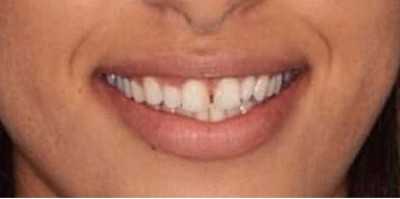

Озеров Петр специализируется на хирургической стоматологии и импланталогии, блестящий специалист по лечению и удалению кисты. Является постоянным участником курсов, семинаров и международных конгрессов по имплантологии и ортопедии. Петр Владимирович проводит протезирование как классическими методиками керамикой и металлокерамикой, так и протезами на драгсплавах (диоксид циркония, алюминий), и эстетическое протезирование винирами и люминирами. Кроме протезирования и имплантации, доктор выполняет и хирургическую подготовку к ним: операции по костной пластике с применением искусственной кости и аутокости (собственной кости пациента).